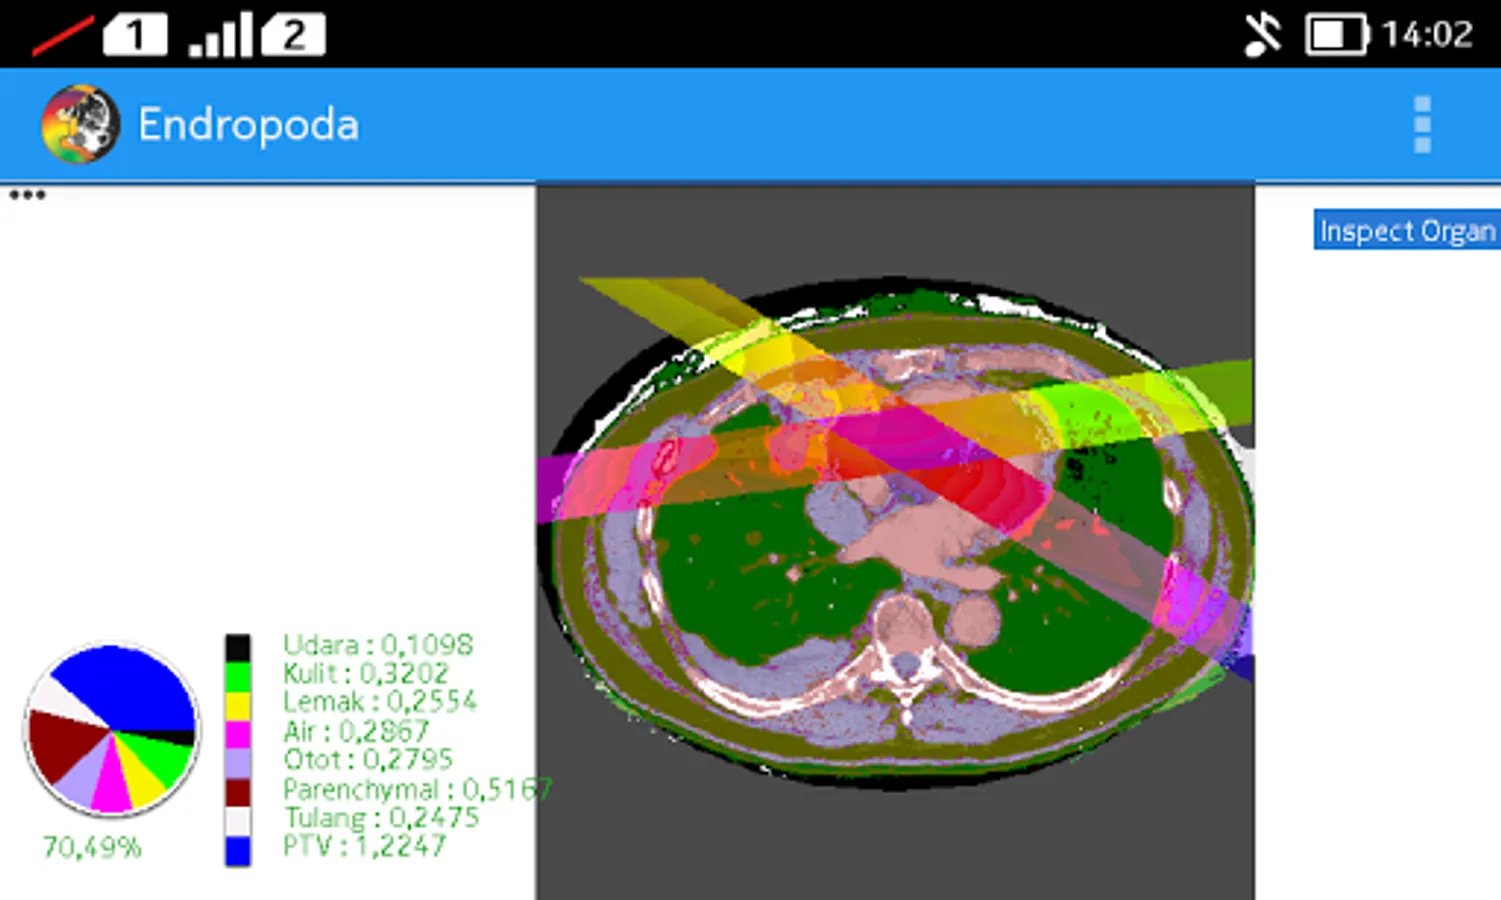

- Apply Beam : User can see the Beam direction for cancer treatment, including the colour distribution describes the absorbed dose

- Inspect Organ : The organ identification will be displayed automatically based on CT Number value that is stored in each pixel of CT-Scan image